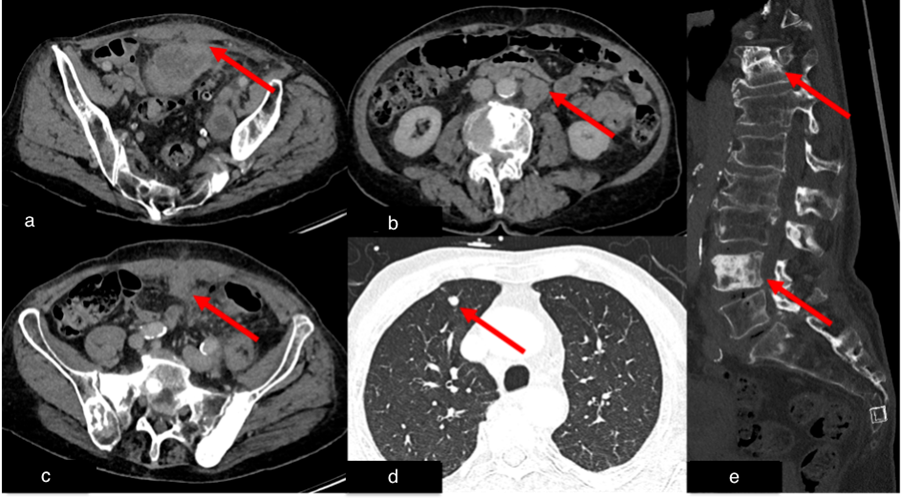

Figure 6.

Case 3, 76-year-old male. Initial chest and abdominal CT to investigate potential infections, including COVID-19 findings, revealed no infectious source. However, there was strong suspicion for metastasized carcinoma: (a) Wall thickening of a urachal remnant raised concern for urachal carcinoma with infiltration of theabdominal wall (red arrow). (b) Enlarged lymph nodes were suspicious for lymph node metastases (red arrow). (c) A peritoneal soft tissue mass suggested peritoneal metastasis (red arrow). (d) A solid pulmonary nodule in the lung raised concern for lung metastases (red arrow). (e) Multiple sclerotic lesions in the spine were indicative of osseous metastasis (red arrow). Histopathological examination following surgical intervention confirmed the diagnosis of metastasized sigmoid carcinoma.